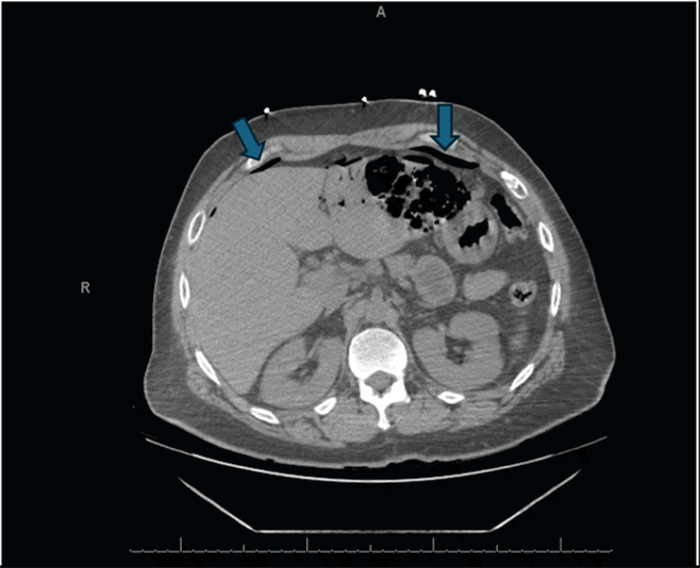

The etiology of pneumoperitoneum in our patient was not a perforated viscus, which might have been anticipated given the CT findings of gastric emphysema. To the best of our knowledge, this is the first reported case of emphysematous gastritis leading to extensive portal venous gas with subsequent transhepatic capsular gas escape causing pneumoperitoneum. The left lobe of his liver was almost entirely replaced by gas and inflammatory collections, a consequence of gas-forming bacteria transported via the portal vein. The reason for the relative sparing of the right hepatic lobe, despite its typically greater portal blood flow, remains unclear. We postulate that the severity of the intrahepatic gas accumulation led to the rupture of the liver capsule, thereby producing the pneumoperitoneum observed on imaging (Figure 5). There are three published case reports detailing post-endoscopic retrograde cholangiopancreatography (ERCP) pneumoperitoneum attributed to severe pneumobilia and hepatic capsule rupture; all three of these patients were managed conservatively.15 However, given our patient's constellation of pneumoperitoneum, portal venous gas, and emphysematous gastritis, exploratory laparoscopy was deemed necessary to definitively exclude ischemic bowel or gastric perforation. Once these were ruled out laparoscopically and viable gastric mucosa was confirmed by EGD, we were reassured that conservative management with drain placement, antibiotics, and serial imaging was appropriate. If presented with a similar case in the future, obtaining a CT abdomen and pelvis with intravenous and possibly a venous phase contrast could be beneficial, potentially providing more information regarding the presence of gas in the arterial system versus confinement to the portal venous system. Furthermore, obtaining gastric mucosal biopsies at the time of EGD for additional microbiological culture and sensitivity data would have been informative.

Figure 5. CT Highlighting Pneumoperitoneum. Published with Permission

Axial follow-up CT scan of the upper abdomen, highlighting the presence of extraluminal free intraperitoneal air